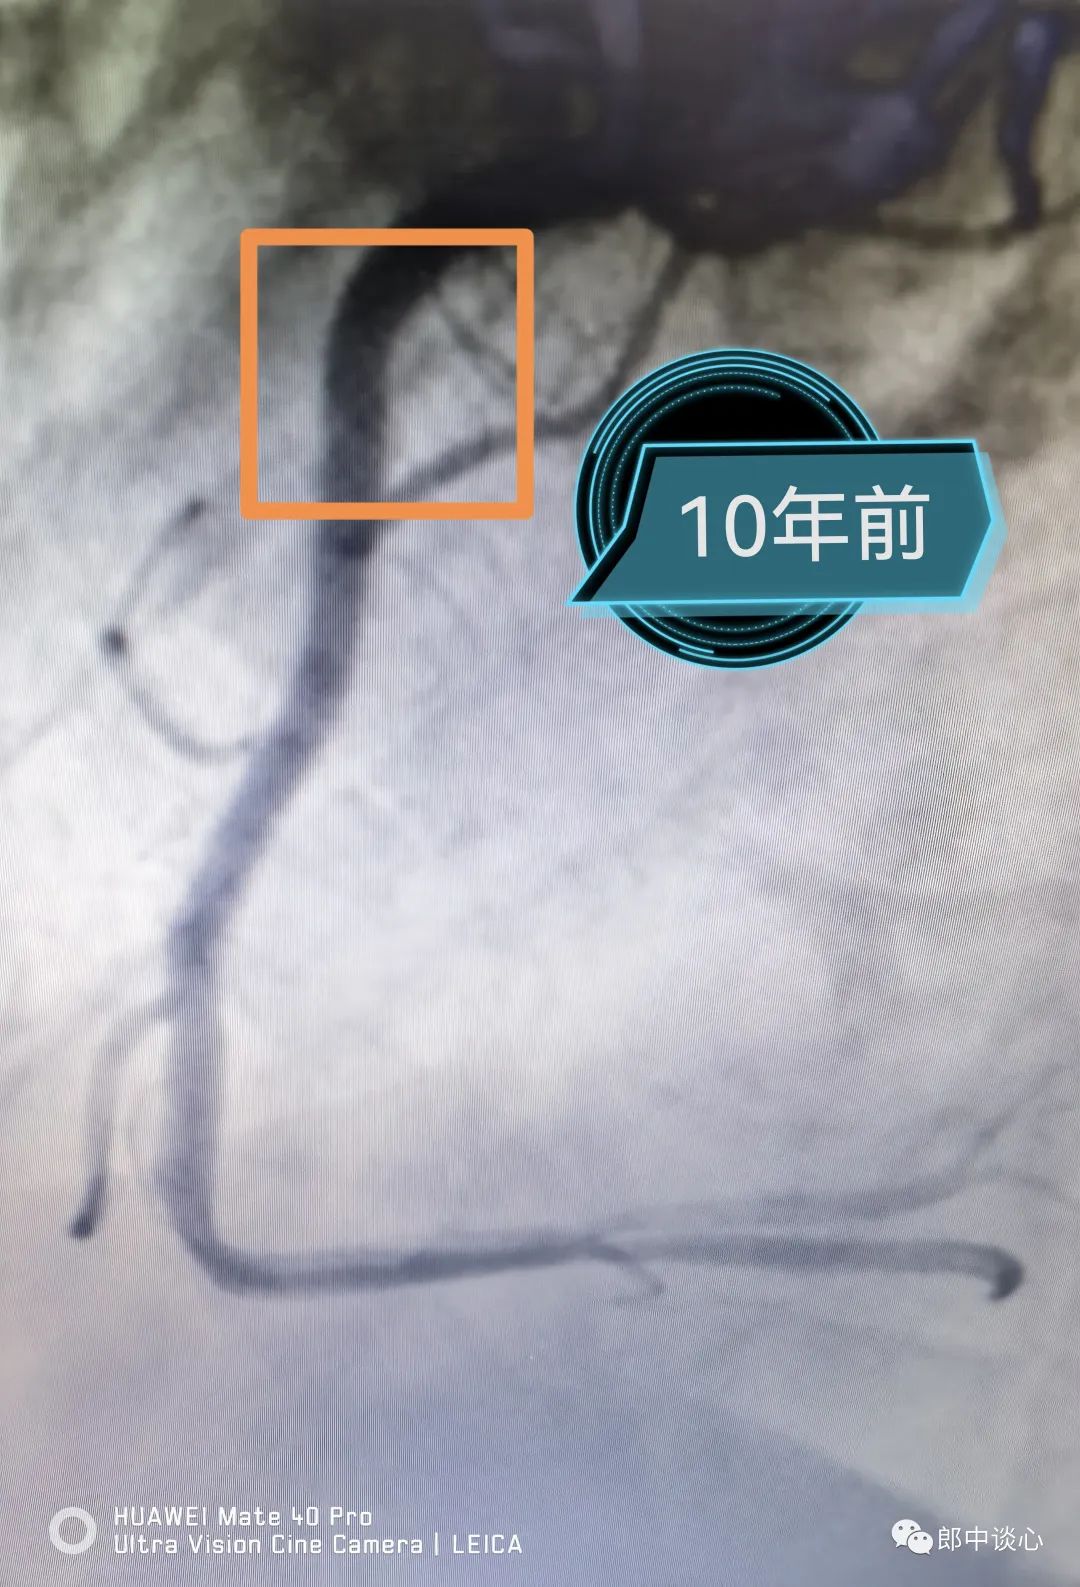

10年前,第一次造影复查,右冠是下面这个样子,这个右冠近段更早有外院植入支架了。